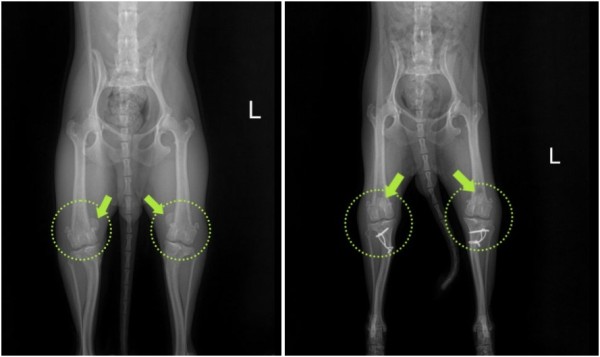

김해 강아지 슬개골 탈구 수술 전문 김해동물메디컬센터ㅣ내측 탈구 4기 MPL 교정술

오늘의 환자는 이전에 양쪽 슬개골 탈구 진단을 받고

관절관련 보조제와 식이를 통한 체충 조절 등을 통해 관리를 해오던 중

최근 자다가도 일어나 빙글빙글 돌아다니며 다리쪽 통증을 호소하는 것 같다며 내원하셨습니다.

정확한 상태 확인을 위한 검사를 진행한 결과,

양쪽 모두 안쪽으로 슬개골이 빠지는 내측탈구 4기 상태가 확인되었고

통증의 근본 원인을 해결하기 위해 양측 모두 슬개골 탈구 교정술(MPL)을 진행하기로 결정하였습니다.

교정술 후 5일간 입원하여 24시간 케어를 받고 양호한 컨디션으로 퇴원한 아이는

집으로 돌아가서도 한동안 평지 생활과 내복약 복용 등 보호자의 세심한 케어와

꾸준한 통원 치료로 현재는 통증 반응 없이 정상 보행으로 생활하고 있습니다!